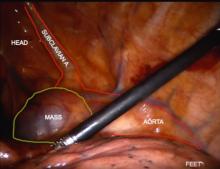

A 35-year-old woman with the chief complaint of chest pain and pressure was referred to thoracic surgery after a mediastinal mass was identified on a chest x-ray. Chest CT confirmed the presence of a 4.6 cm mass adjacent to the aorta and superior to the left main pulmonary artery. PET/CT imaging identified a smooth mass lateral to the aortic arch and superior to the left main pulmonary artery, which was found to be FDG-avid with a max SUV of 8.14. The patient underwent robotic resection for diagnosis and treatment. Histological examination revealed expansion of mantle zones with concentric rings of lymphocytes, characteristic of localized Castleman disease, hyalin vascular type. The patient's postoperative course was uneventful, and she was discharged on postoperative day two with oral analgesics for pain management. At the two-week follow-up visit, the patient was doing well. She will have long-term follow up with hematology.